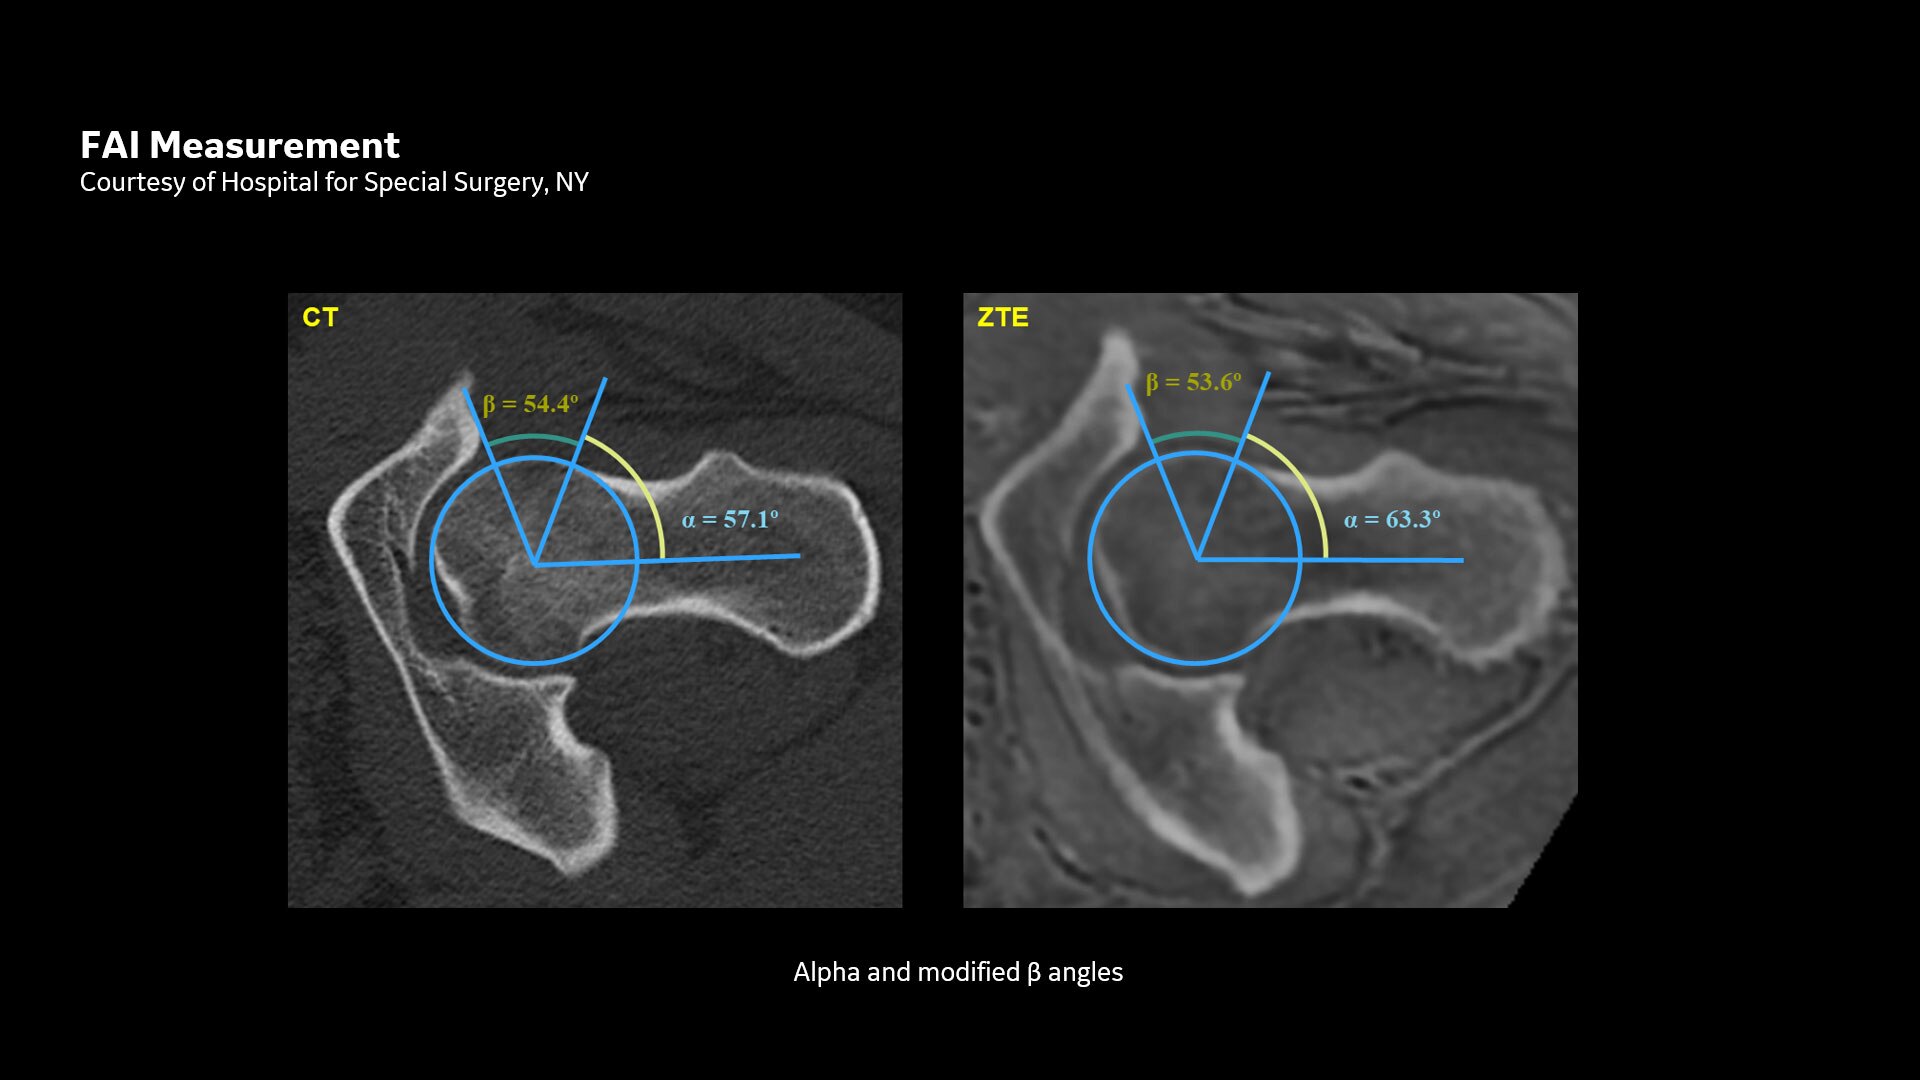

Geometric measurement with oZTEo

oZTEo images can be used for geometric and morphologic measurements, such as in routine FAI in the hip.  These results have been published in The American Journal of Sports Medicine, 2019: 47(14):  3460-3468.

https://journals.sagepub.com/doi/10.1177/0363546519878170